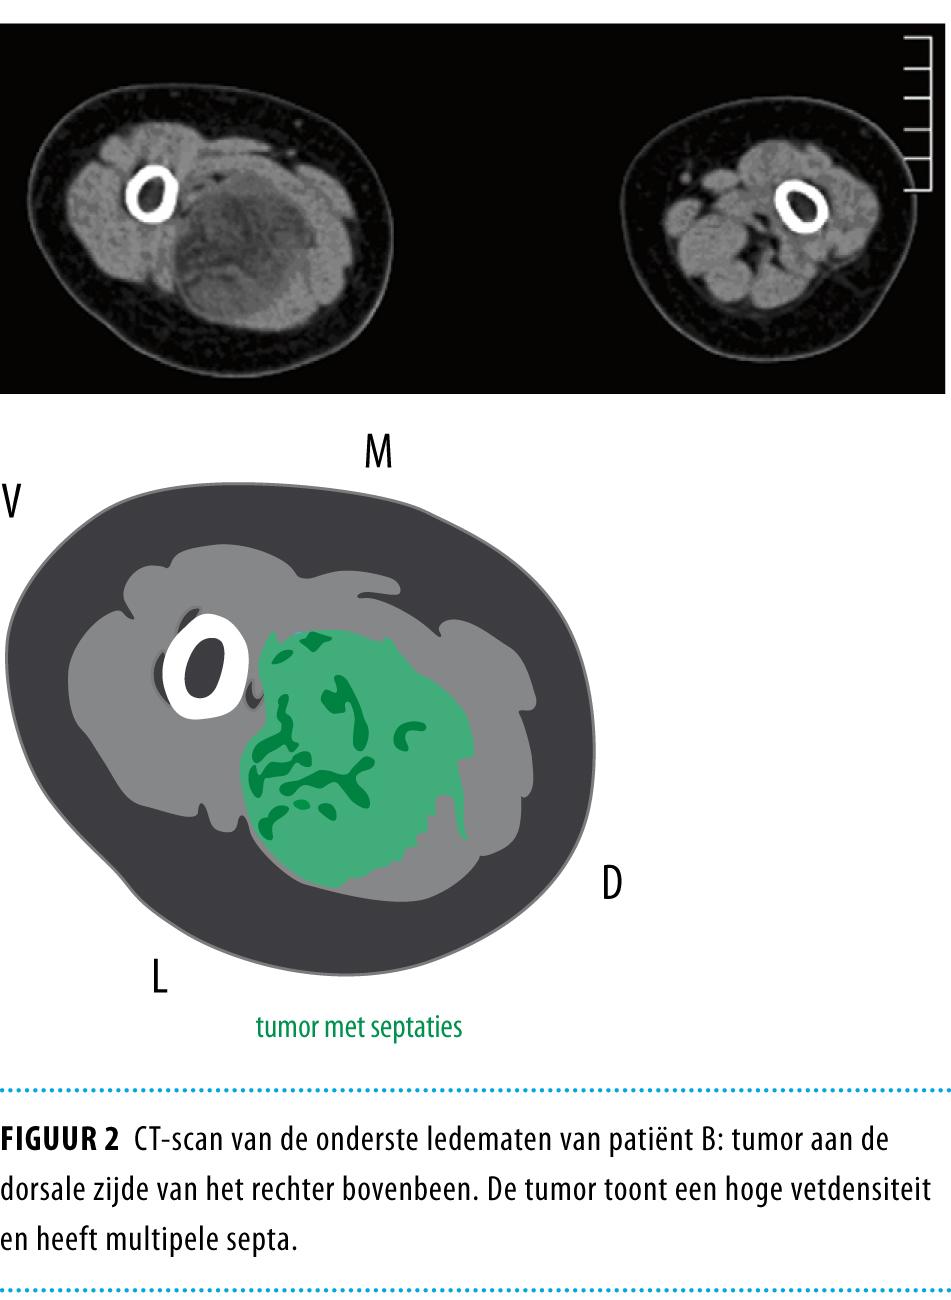

Patiënt A, een meisje van 6 maanden oud, werd opgenomen op de afdeling Kindergeneeskunde in een perifeer ziekenhuis vanwege toenemende dyspneu. Een thoraxröntgenfoto toonde een grote massa in het linker mediastinum, met een deviatie van de trachea naar rechts (figuur 1). Patiënte werd onmiddellijk doorverwezen naar een academisch ziekenhuis. Aldaar werd na een naaldbiopsie de diagnose ‘lipoblastomatose’ gesteld. Een volledige resectie bleek niet mogelijk aangezien de tumor tussen de verschillende onderdelen van de plexus brachialus gelokaliseerd was. Postoperatief had patiënte een linkszijdig syndroom van Horner en een geringe parese van de rechter arm. Na een follow-up van 3 jaar waren beide symptomen nog steeds aanwezig.

Figuur 1